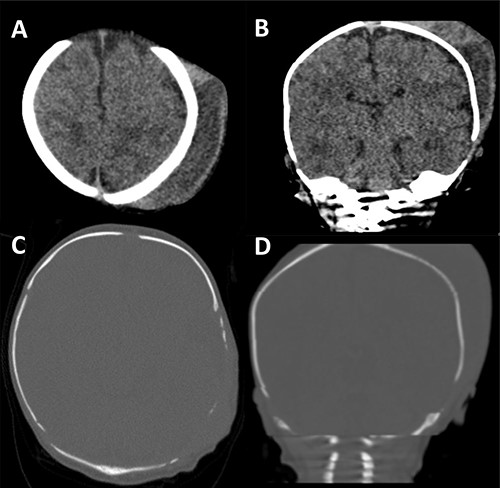

The collection was tapped, and pus was aspirated and sent for microscopy, culture and sensitivities. Gram negative rods were seen in the aspirate and a surgical evacuation was performed. A left parietal incision over the dome of the collection was performed, the pus evacuated and copious irrigation with warm Ringer’s solution and hydrogen peroxide was performed, followed by debridement of the space and underlying bony surface (Fig. 3). Escherichia coli was cultured from both pus and bone samples and S. epidermidis was cultured from the blood. Following the procedure, the patient improved with no further fevers and with a progressive decrease in CRP. He received 3 weeks of intravenous antibiotics followed by oral ciprofloxacin for a week. He was discharged home 20 days after surgery. Repeat CT and magnetic resonance imaging (MRI) of the head revealing no complications (Fig. 4).

CT scan and MRI taken of the patient upon discharge. In all images, a well-defined skull with no thinning is illustrated and with a resolved haematoma.